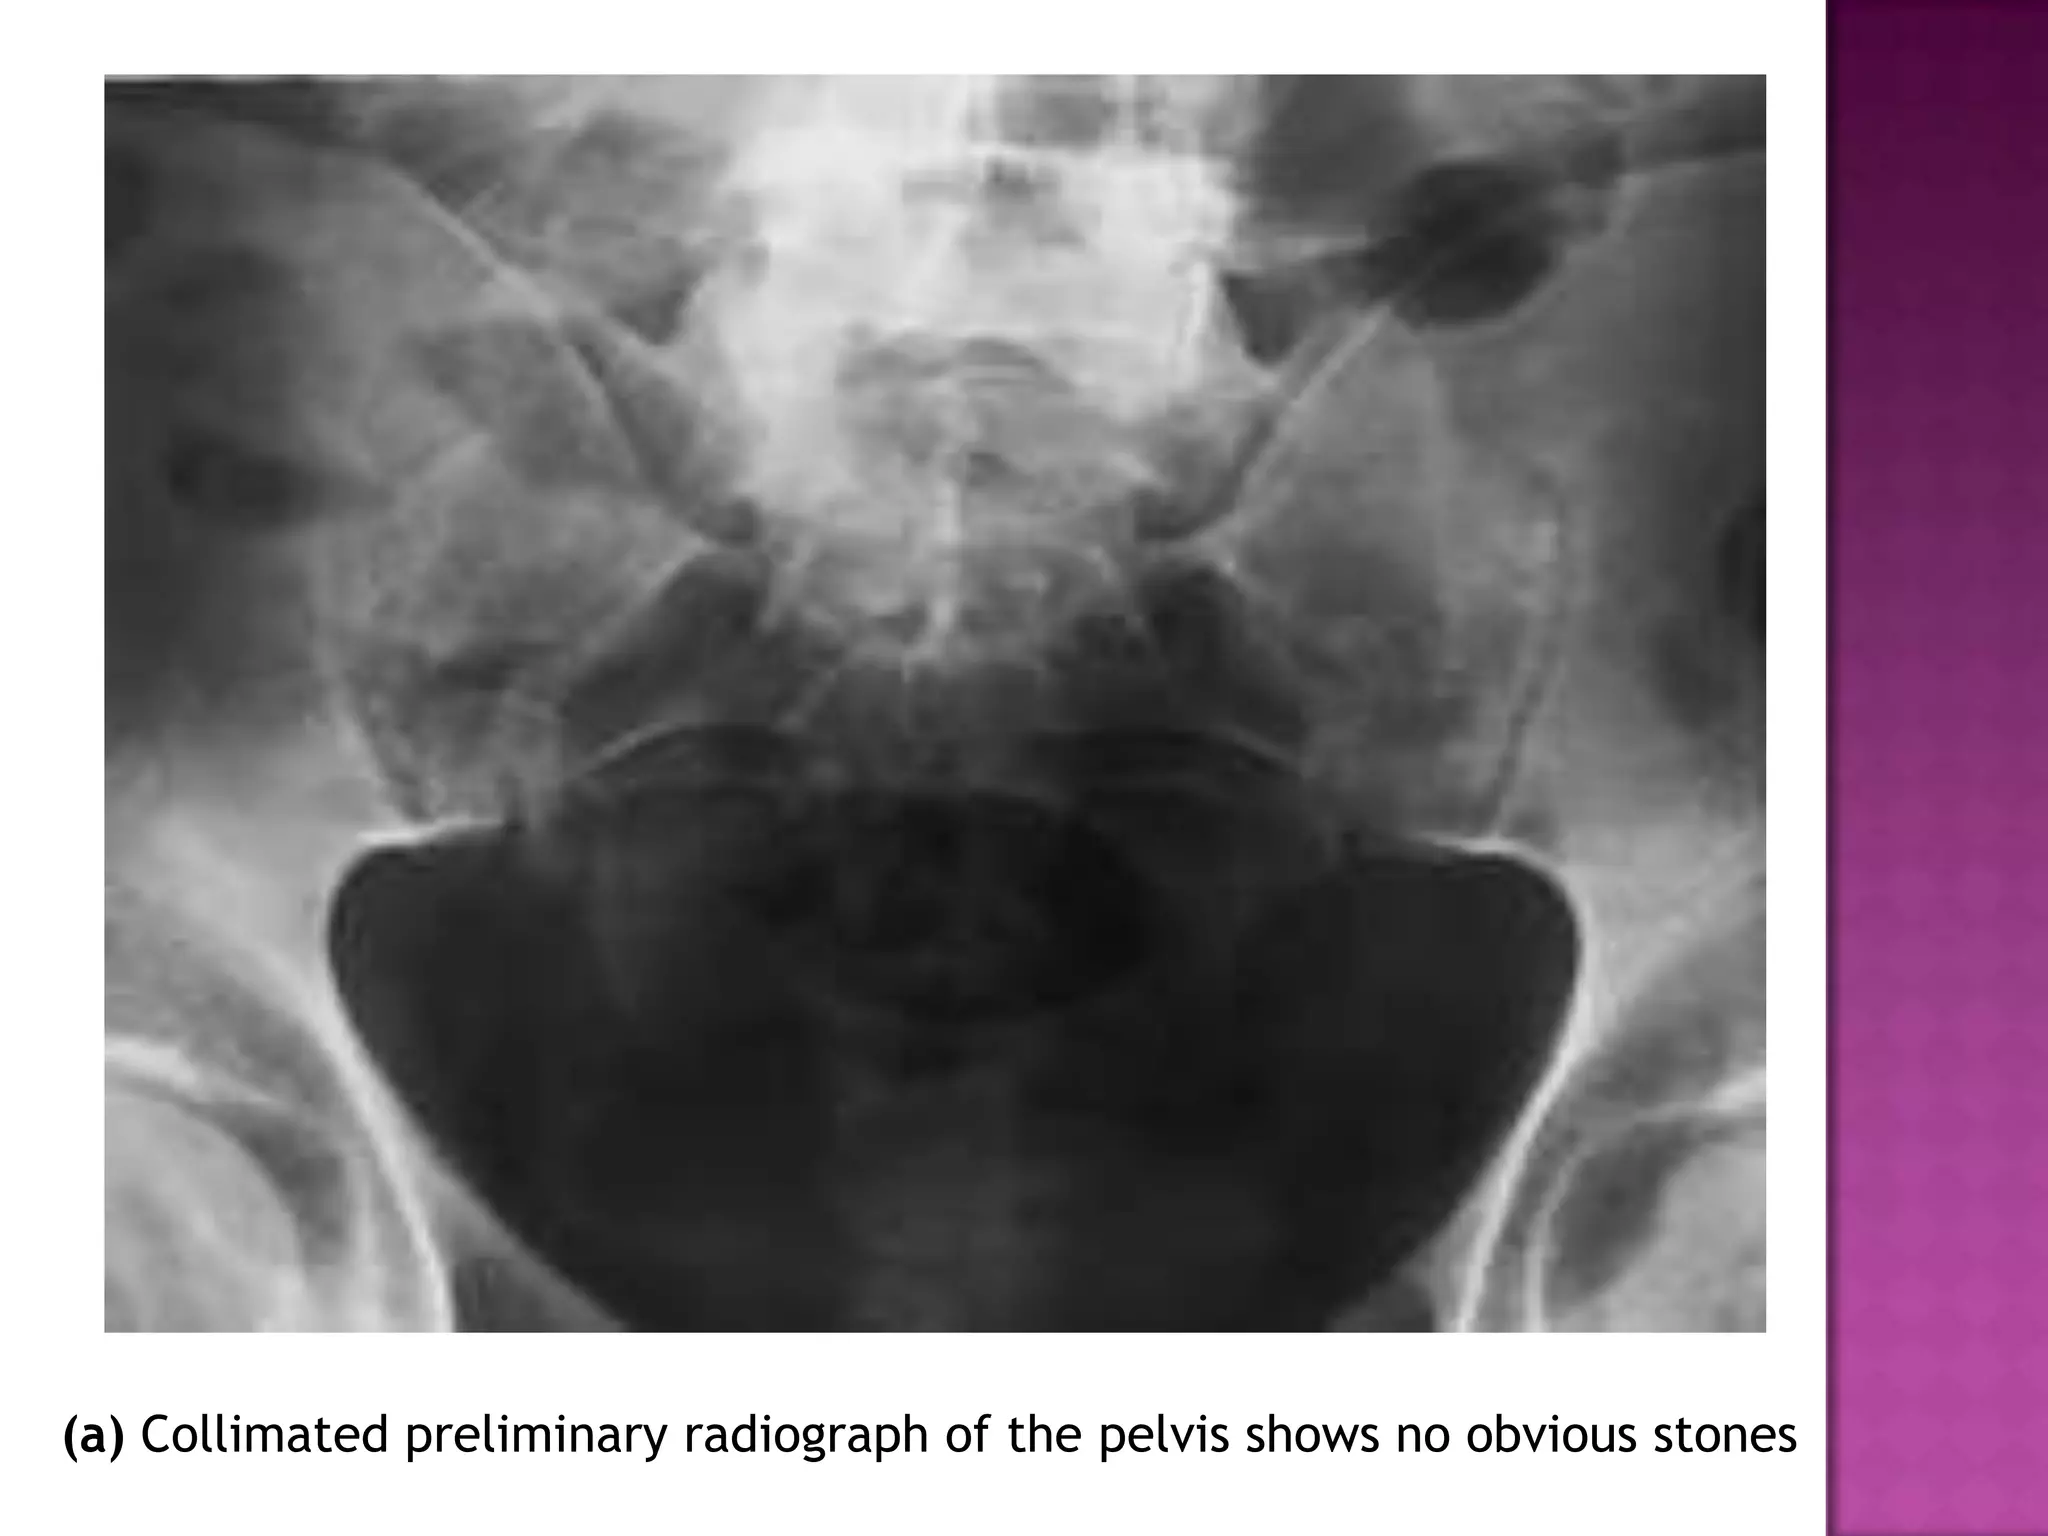

(a) Collimated preliminary radiograph of the pelvis shows no obvious stones

(a) Collimated preliminaryradiograph of the pelvis shows no obvious stones